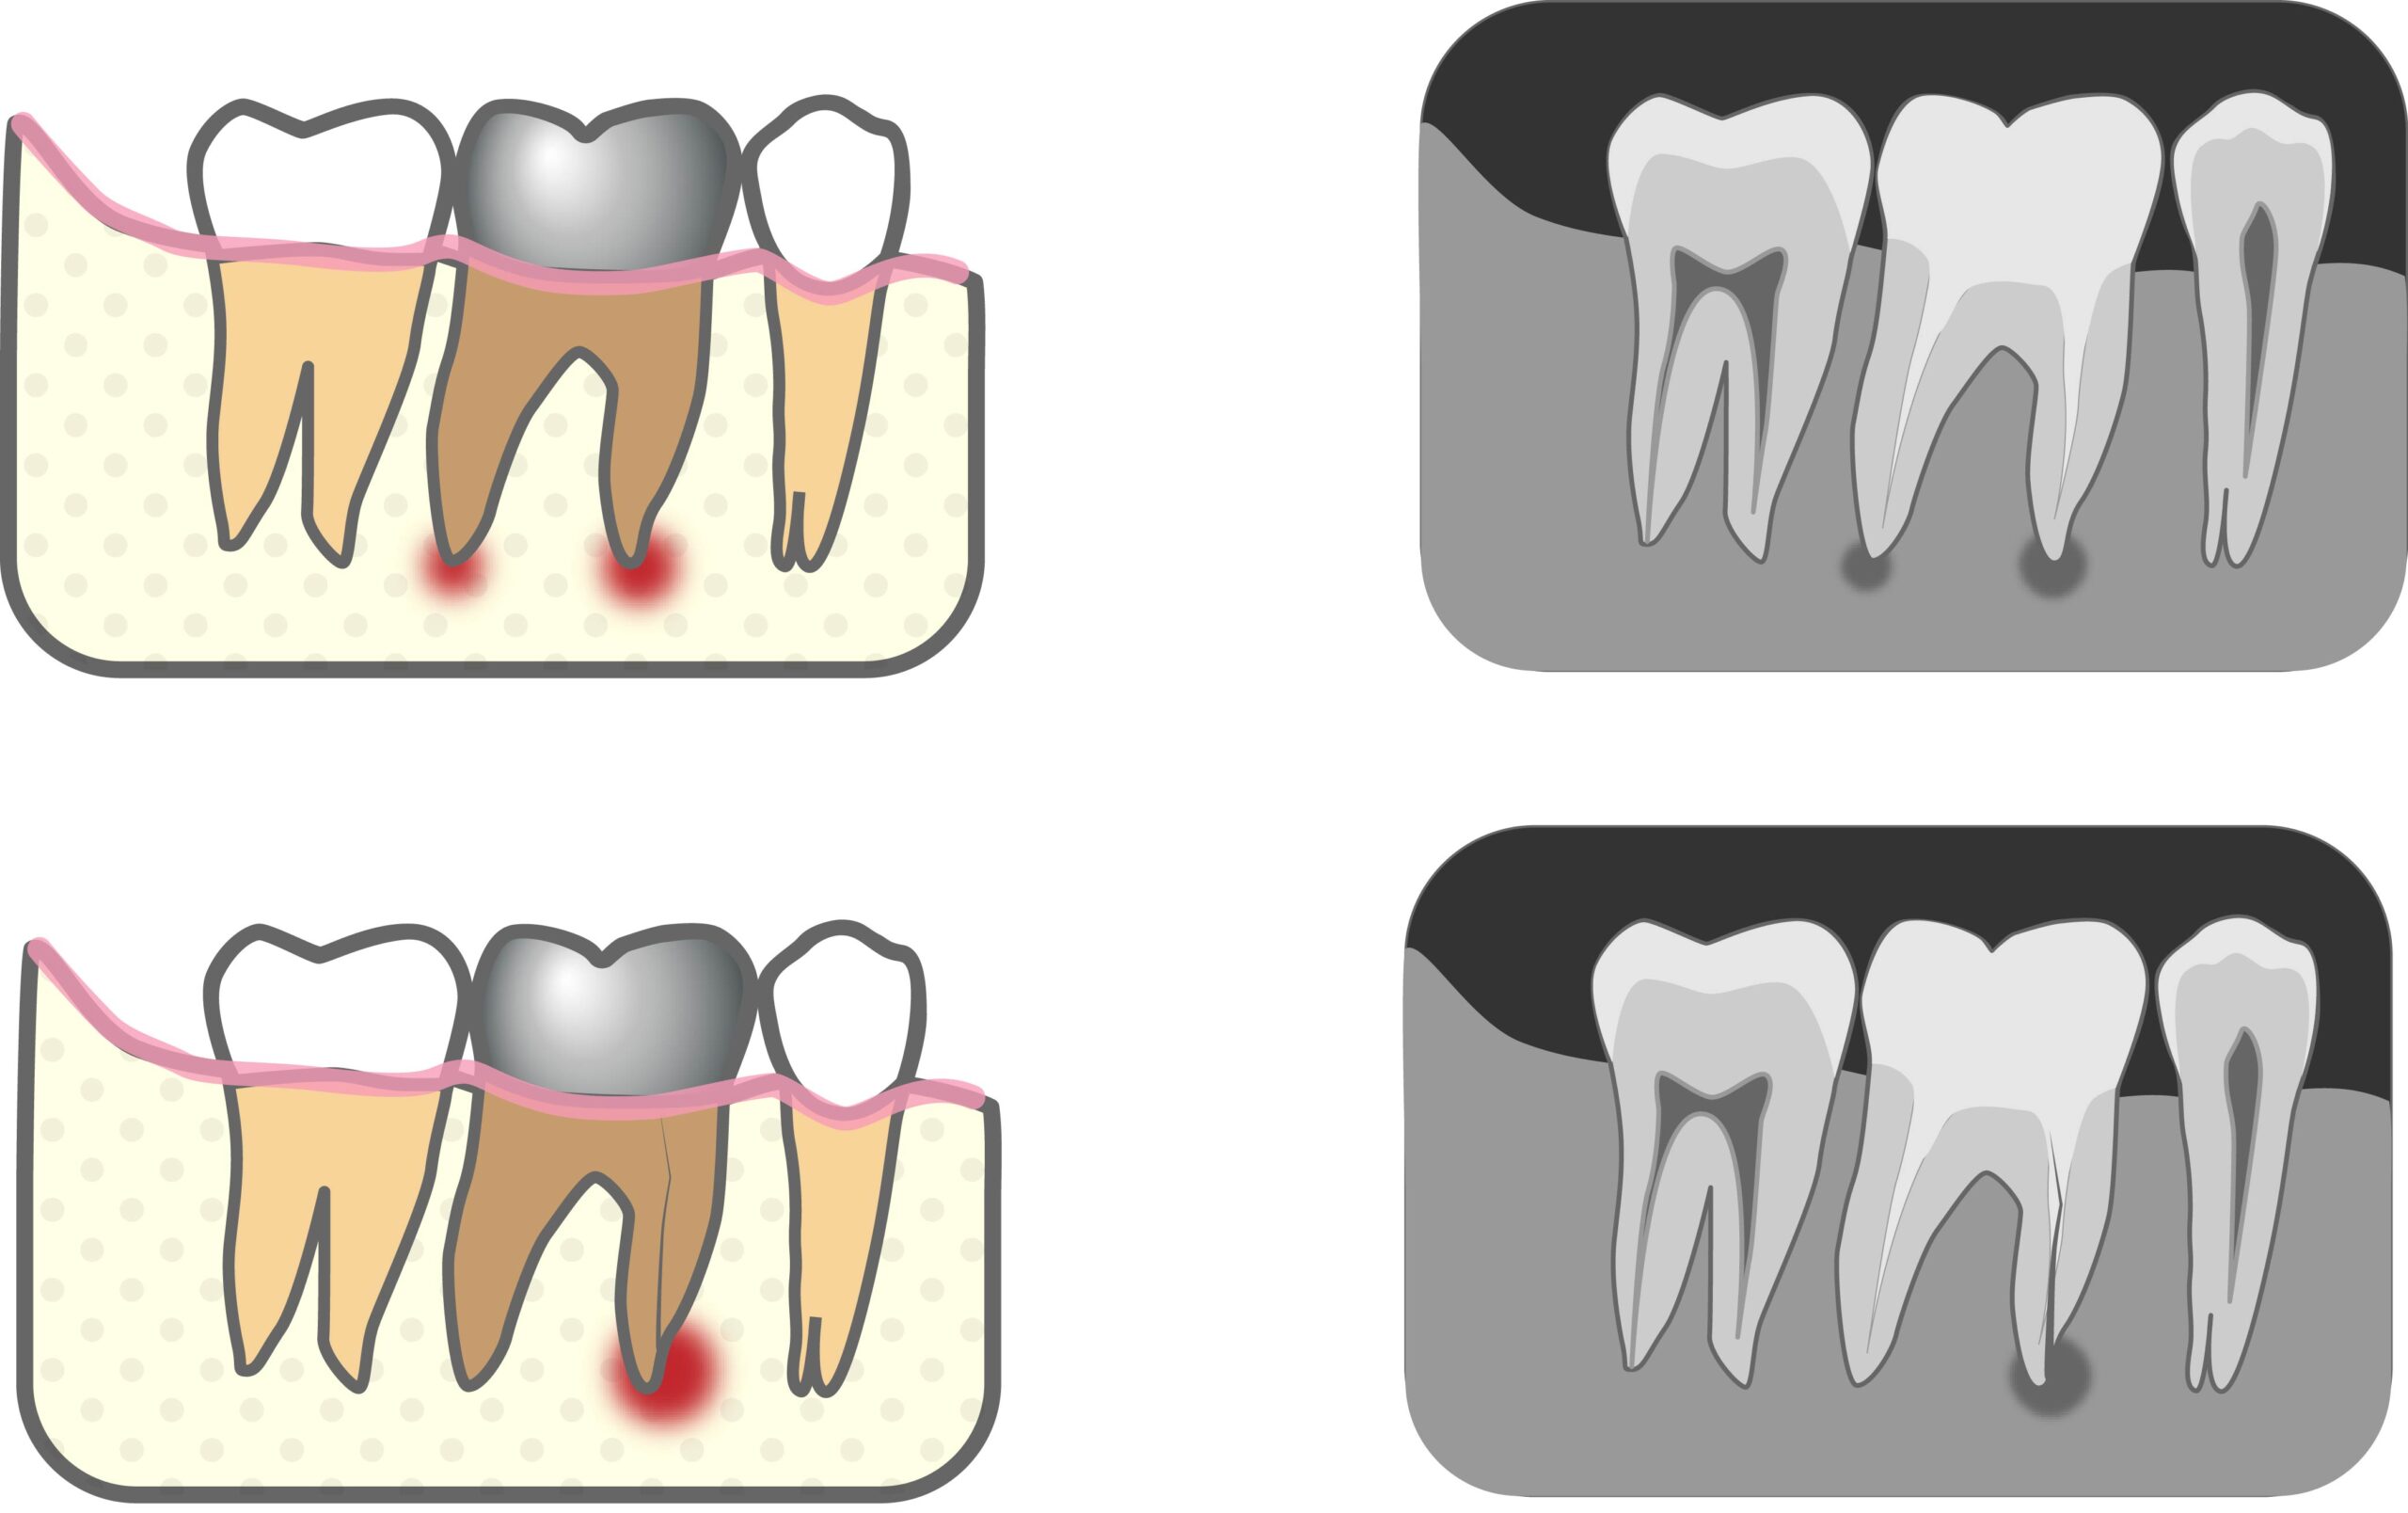

根尖嚢胞とは歯の根の先(根尖)にできる袋状の病変のことです。袋の中には膿や液体がたまり、多くは虫歯の放置・神経が死んだ歯が原因で起こります💦

神経が死んで放置していると根の先に細菌が残り、体が細菌を閉じ込めようとして袋(嚢胞)を作ることでできます。

ほとんど無症状で進行すると歯ぐきにニキビみたいなできものができたり大きく腫れたりします。他に噛むと違和感だったり顔が腫れることもあります🥶💦

痛みがないからと放置すると歯を残せる確率も低くなります!定期検診でレントゲン写真を撮ったり、歯茎が腫れているな…と思ったら自己判断せず一度歯科で診てもらいましょう!☺️